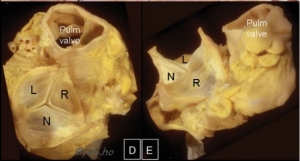

Unicuspid and quadricuspid configurations (Fig 5) are less common than bicuspid valves.

Tricuspid, bicuspid

unicuspid

quadricuspid valves

Fig 5: Tricuspid, bicuspid, unicuspid and quadricuspid valves